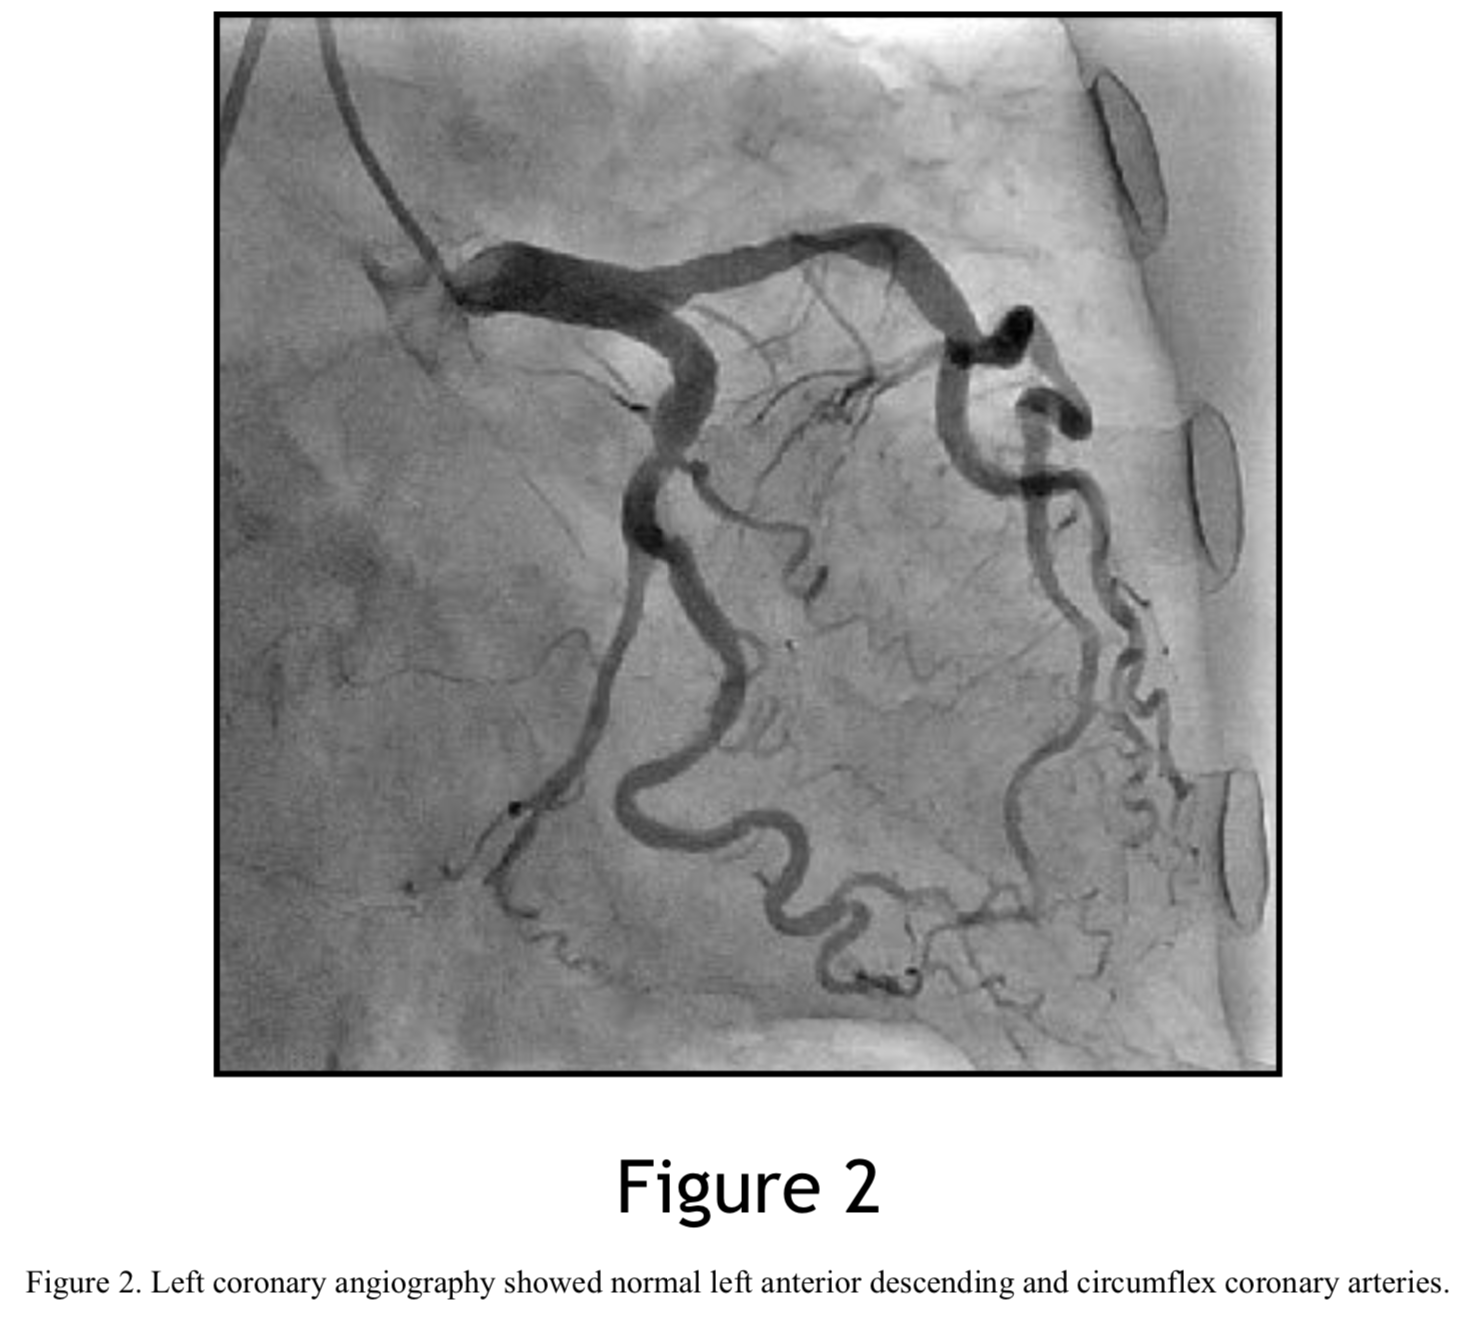

チョロQ MEN'S ROMAN めざまし OFFLINE PARTY LIMITED スカイラインGT-R KPGC-10 (Q00, Bonus Online Case: A Novel Use of Dio Catheter for Delivery of Rotational Atherectomy Burr in Tortuous Coronary Artery

Bonus Online Case: A Novel Use of Dio Catheter for Delivery of Rotational Atherectomy Burr in Tortuous Coronary Artery